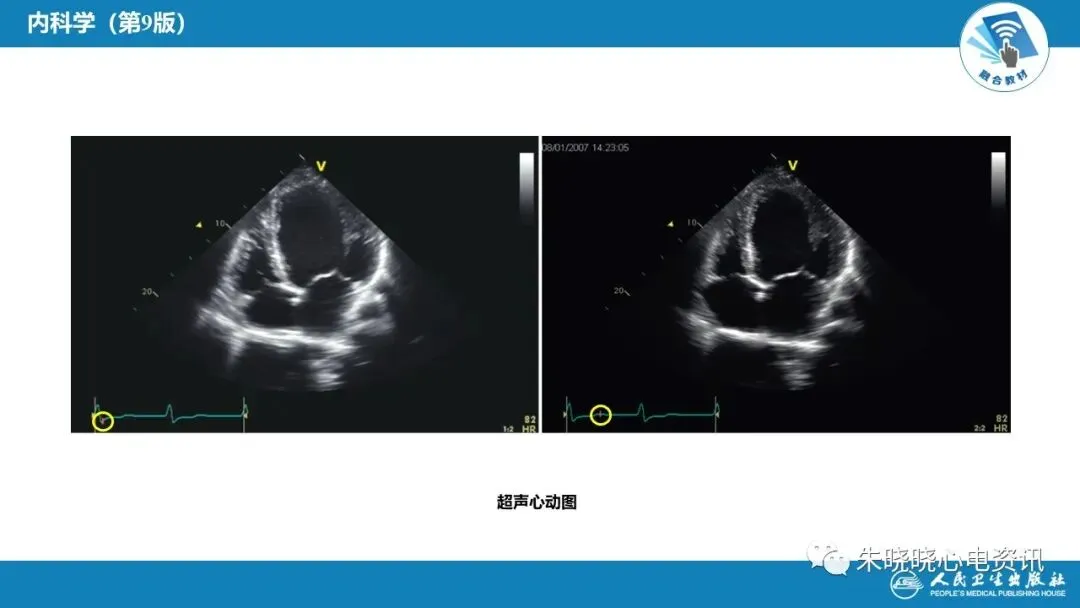

心力衰竭(PPT)